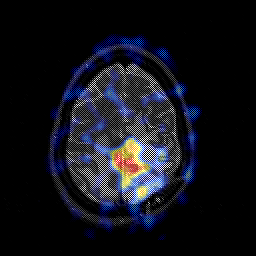

Glioblastoma multiforme overlay -- Slice #41

[Home][Help][Clinical][Tour 1][Tour 2][Tour 3] Slice 41